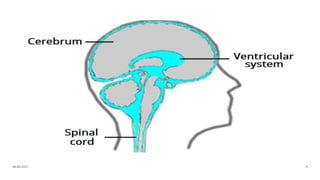

Anatomy of brain

Anatomy of ventricles